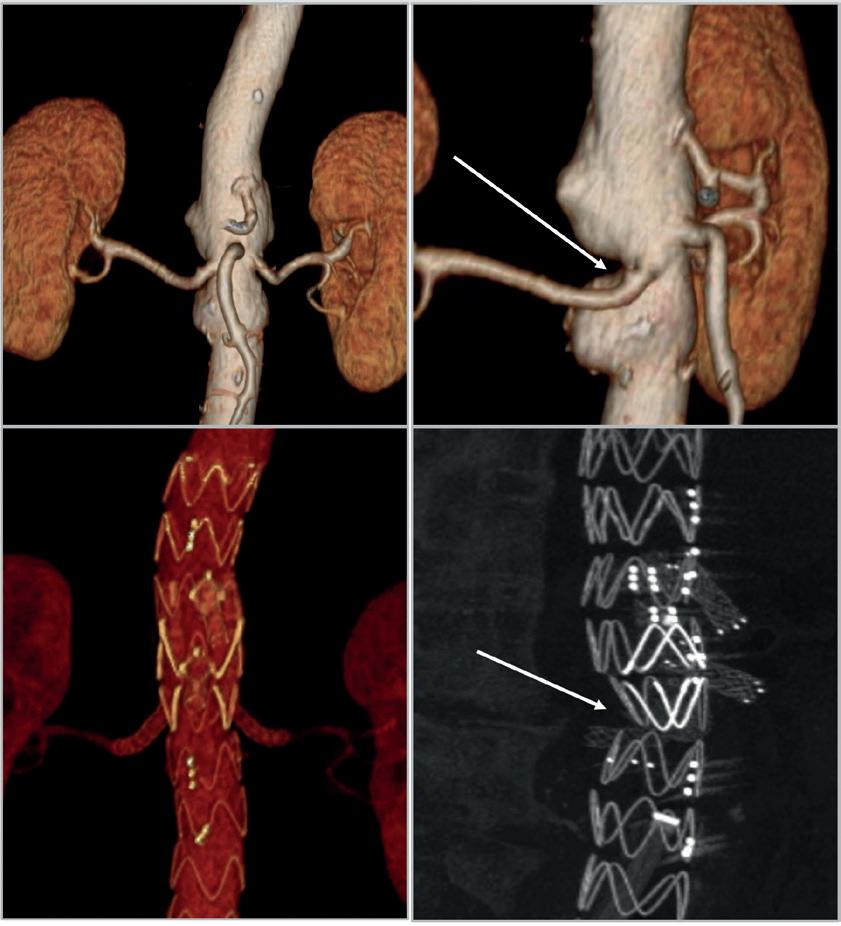

Michele Piazza (Padua, Italy) advises how to manage the challenging anatomical scenario of a narrow aorta during fenestrated and branched endovascular aneurysm repair (F/BEVAR), highlighting accurate, patient-specific planning and use of the correct bridging stent technology as the keys to good results.